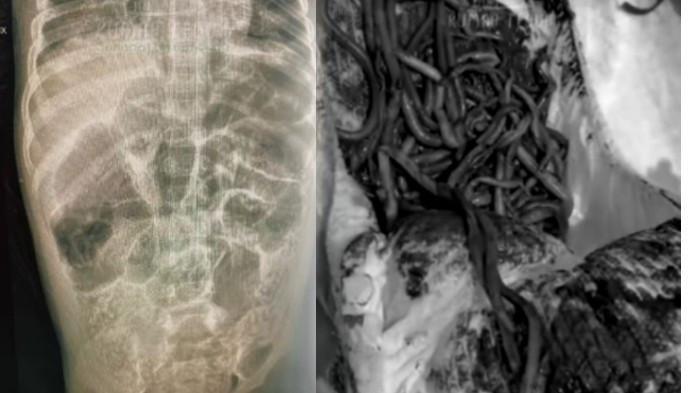

Tribunlampung.co.id, Bandar Lampung - Dinas Kesehatan (Diskes) Provinsi Lampung menggencarkan upaya pencegahan kasus cacingan pada anak.

Hal itu menyusul kasus kematian seorang anak di Jawa Barat akibat infeksi cacingan parah.

Lonjakan ini terjadi menyusul viralnya kasus bayi meninggal dunia akibat cacingan di Jawa Barat.